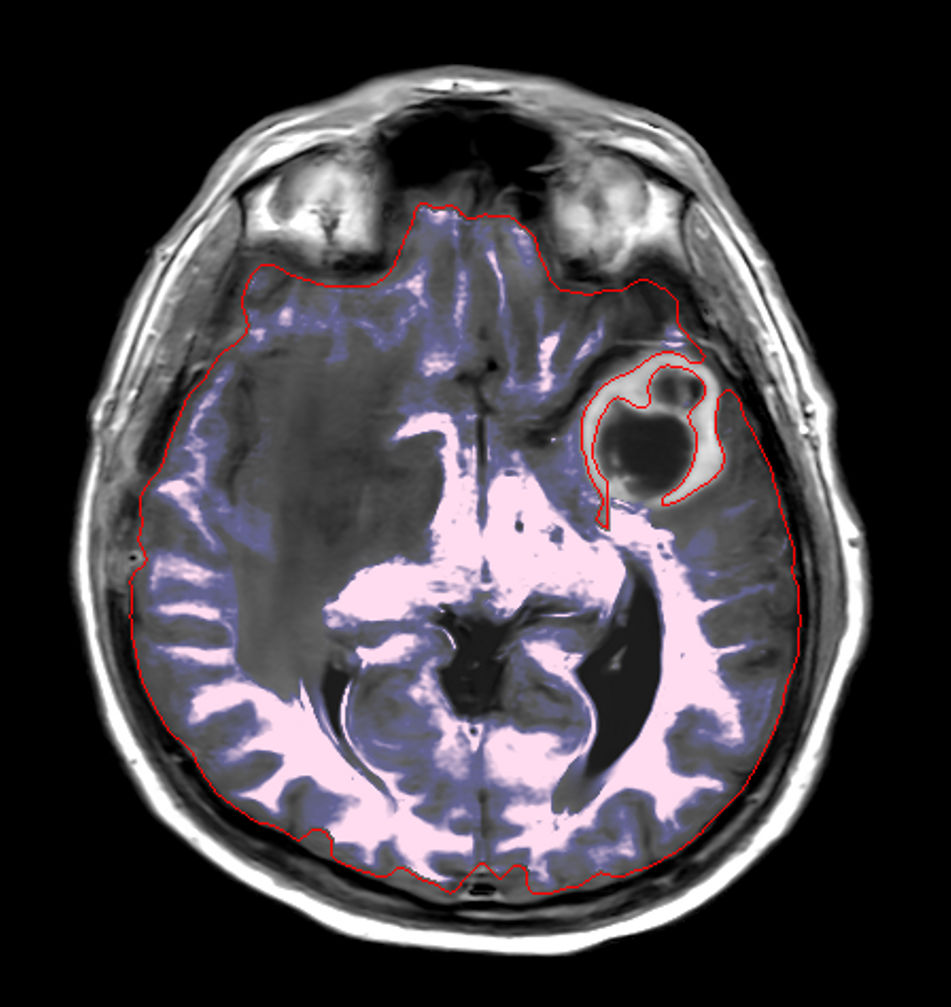

Patient with a large brain lesion. AI based SmartSpeed is utlized to shorten scan time without compromise in image quality. Advanced imaging techniques like pCASL and 3D APT are used to perform contrast-free brain imaging to assess perfusion and tumoral activity. SWIp 3D susceptibility weighted offers the high sensitivity required to visualize deoxygenated (venous) blood or calcium deposits. A single synthetic (SyntAc) brain quantification scan is added. The resulting data of this scan can be used as input for advanced third party processing software* to synthesize MR images with different contrasts, brain parenchyma fraction maps and/or brain segmentation maps.

Axial SyntAc

Axial SyntAc (Grey Matter)

Axial SyntAc (White Matter)

Axial SyntAc (CSF)